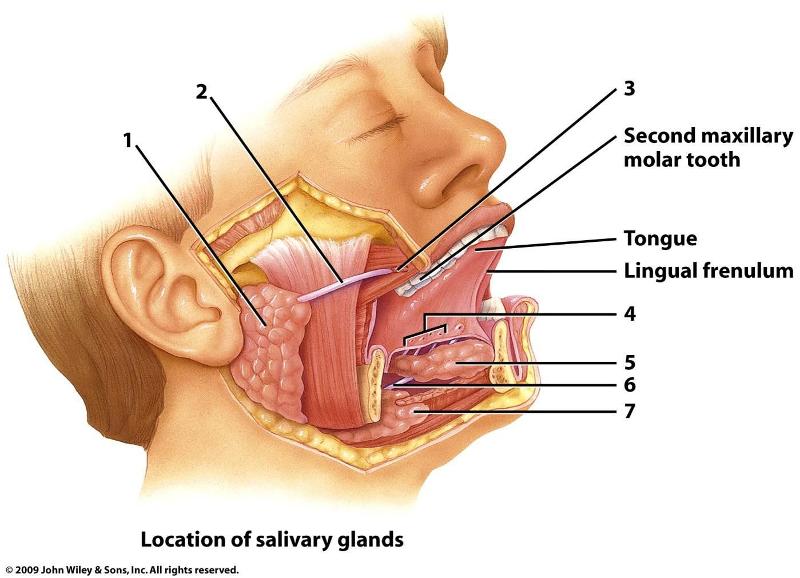

Parotid gland

Sublingual gland

Submandibular gland